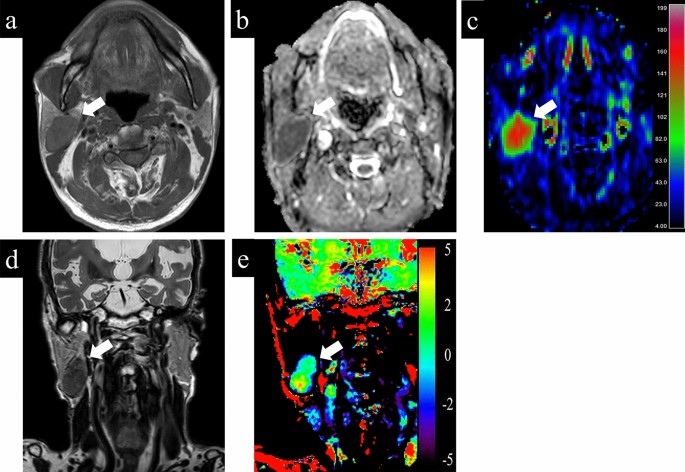

Representative cases with parotid gland lesions are shown in Figs. 4, 5, 6. Typical pleomorphic adenomas show low TBF, which makes it difficult to distinguish from malignant lesions, while present high ADC and low APT which suggest benign lesions (Fig. 4). On the other hand, Warthin tumors have low ADC, which makes it difficult to distinguish from malignant, while presenting high TBF and low APT, which is consistent as benign (Fig. 5). Most malignant lesions showed high APTSI, low ADC, and moderate TBF (Fig. 6).

A 79-year-old male with Warthin tumor. (a) T1-weighted image shows a homogeneous low intensity lesion in the right parotid gland. Apparent diffusion coefficient (ADC) (b) and tumor blood flow (TBF) (c) maps show the lesion with the mean ADC value of 0.85 × 10−3 mm2/s and the mean TBF value of 133.06 mL/100 g/min, respectively. On T2-weighted coronal image (d), the lesion shows lower signal intensity than the adjacent parotid gland parenchyma. Amide proton transfer (APT) (e) map shows the lesion with the mean APT-related signal intensity of 1.24%. An arrow in each image indicates the lesion.